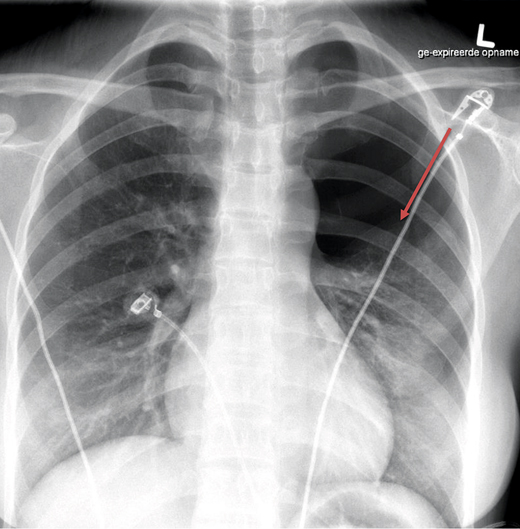

Een 33-jarige vrouw bezocht de huisarts wegens pijn op de borst. Een dag eerder had zij een acupunctuurbehandeling ondergaan voor pijnklachten in de rug. Daarbij waren naalden geplaatst op onder meer de rug en de schouders. Vlak na deze behandeling kreeg de patiënte last van nieuwe pijnklachten in de rug, later ook op de borst. De pijn op de borst werd erger bij diepe inademing en er was sprake van dyspneu. Bij auscultatie van de longen was links verminderd ademgeruis hoorbaar en aan de linkerzijde van de thorax was er een hypersonore percussie. De patiënte had een regulaire tachycardie van 110/min en een saturatie van 100%. De huisarts verwees haar door voor een röntgenfoto van de thorax. De beschrijving van de radioloog luidde: pneumothorax links apicaal en ventraal; geen aanwijzingen voor een spanningscomponent; rechterlong goed ontplooid, slank cardiomediastinum. De patiënte bezocht de Spoedeisende Hulp, waar een thoraxdrain geplaatst werd zonder dat er verdere complicaties optraden [figuur 1].

Figuur 1 | Voor-achterwaartse X-thorax met de pneumothorax (rode pijl)

Voor-achterwaartse X-thorax met de pneumothorax (rode pijl)